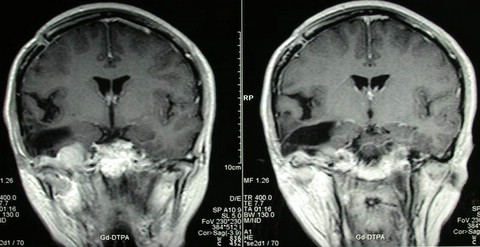

女性,29岁,主因头痛恶心呕吐1个月入院。查MRI示:右侧中颅底巨大脑膜瘤。

术中显微手术全切肿瘤。术后无加重神经功能障碍。术后图片如下: